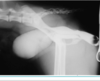

what is this?

Dilation of renal pelvis

Chunky ureters

What is going on?

Hydronephrosis/ dilated ureters